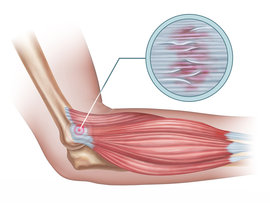

Tennis elbow is a frustrating condition that can occur in tennis players from overuse of their dominant arm; however, anyone can suffer from this elbow condition due to repetitive activities.

If you’re experiencing persistent pain toward the outside of your elbow, especially when you move it or grip something, the licensed physical therapists at Iron City Physical Therapy can help develop pain management regimens to bring you relief and prevent it from coming back.